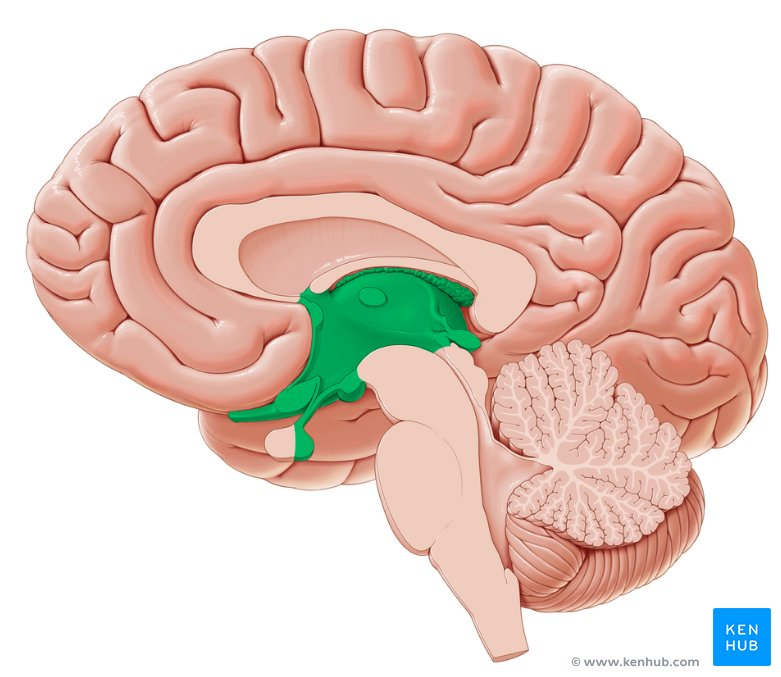

Trace CSF flow from Ventricles to Fourth Ventricle

Lateral Ventricles —> interventricular foramen—>Third Ventricle—> Cerebral aqueduct—>fourth ventricle

After leaving the Fourth Ventricle, where does the CSF go

It flows to the central canal or around the subarachnoid space to leave the brain

How is excess CSF drained?

flows into the arachnoid villi where it is drained into dural venousus sinus with the blood